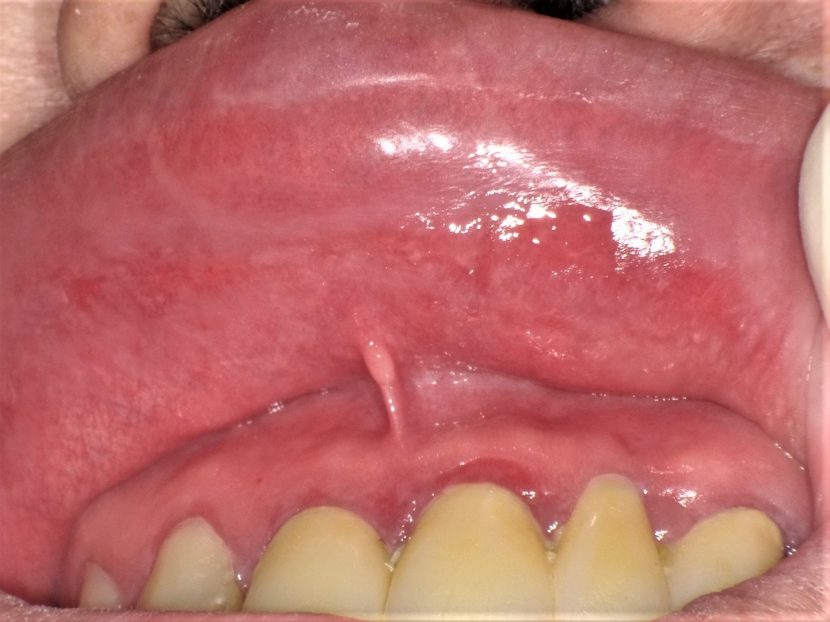

ニコチン性口内炎 舌 (461 無料写真)

ニコチン性口内炎 舌